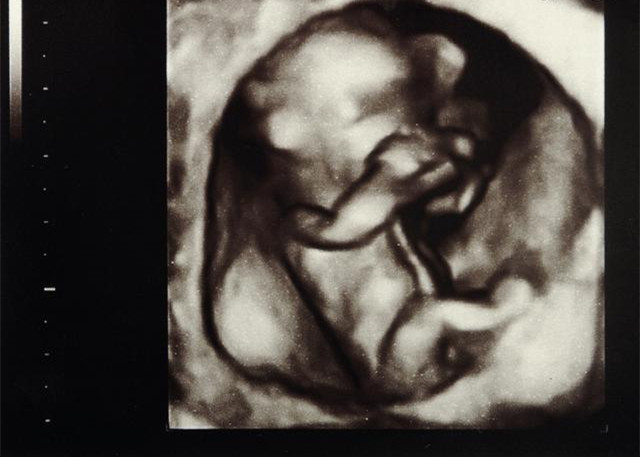

这几周胎儿的如何发育的?

1、胚芽正在子宫深处迅速生长,这时候胚胎宝宝长度约0.4~0.5厘米,有一个小苹果籽大小,但是看起来还不像人,更像一只小蝌蚪。2、本周胎儿的心脏开始有规律的跳动及供血。细胞迅速分裂,主要的器官如肾脏和肝赃开始生长。连接脑和脊髓的神经管也开始工作,原肠开始发育。

3、胚胎的上面和下面开始形成肢体的幼芽,将来形成宝宝的手和腿。

4、面部器官本周开始形成,鼻孔可清楚地看到,眼睛的视网膜也逐步成型。

5、将来形成嘴巴的地方的下方有些小的皱摺,它以后会发育成宝宝的脖子和下巴。

结语:怀孕是个漫长的过程,刚开始大家都难以置信,肚子里原来有个小东西,在两个月的时候,胎儿已经以然成形,用眼睛是看不到的,孕妈妈只能用内心去感受,用B超去观察。